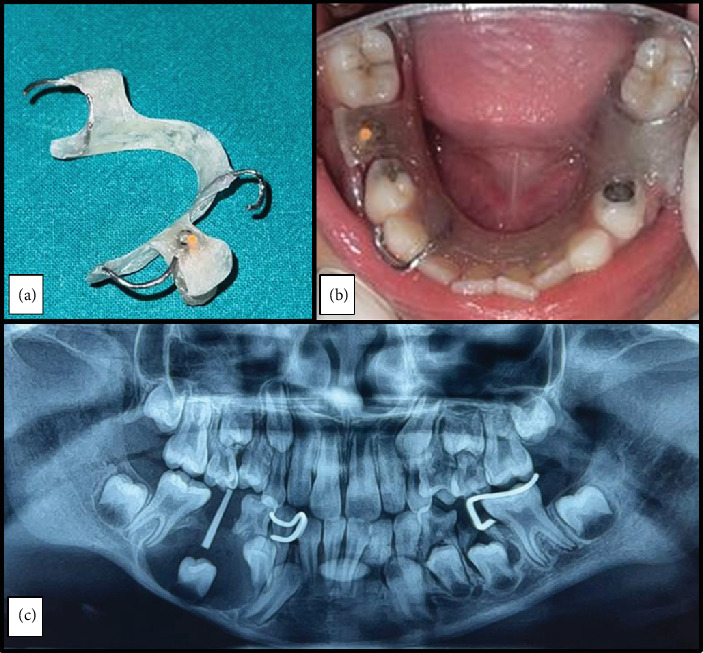

牙源性囊肿(dc)是一种牙源性囊肿,通常与未出牙或阻生牙的牙冠有关,通常在牙长得很大或感染时发现。虽然在成人中很常见,但在儿童中很少发生。大多数儿童病例是在常规乳牙感染x线检查中偶然发现的。治疗方法因病变的大小和范围而异,剜出和有袋化是常用的方法。尽管技术不同,总体预后和治疗结果通常是有利的。本病例报告描述了一名8岁女性通过有袋化结合定制丙烯酸闭孔成功保守治疗下颌骨DC。

Dentigerous cysts (DCs) are odontogenic cysts typically associated with the crowns of unerupted or impacted teeth and are usually discovered when they reach large sizes or get infected. Although common in adults, their occurrence in children are rare. Most cases in children are incidentally discovered on routine radiographic examination of infected deciduous molars. Treatment methods vary based on the size and extend of the lesion, with enucleation and marsupialization being the commonly employed approaches. Despite the variation in techniques, the overall prognosis and treatment outcomes are generally favorable. This case report describes the successful conservative management of a mandibular DC in an 8-year-old female through marsupialization in conjunction with a custom-made acrylic obturator.